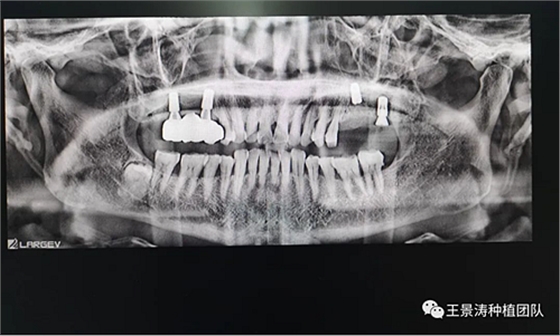

患者左側(cè)16慢性根尖周炎,17缺失。16根尖炎癥距上頜竇底較近,需內(nèi)提升,但是因?yàn)閮?nèi)提升后骨質(zhì)較薄所致植入深度過深,埋入式植入。17非埋入式種植。后期效果均可。

術(shù)后一周

二期手術(shù)